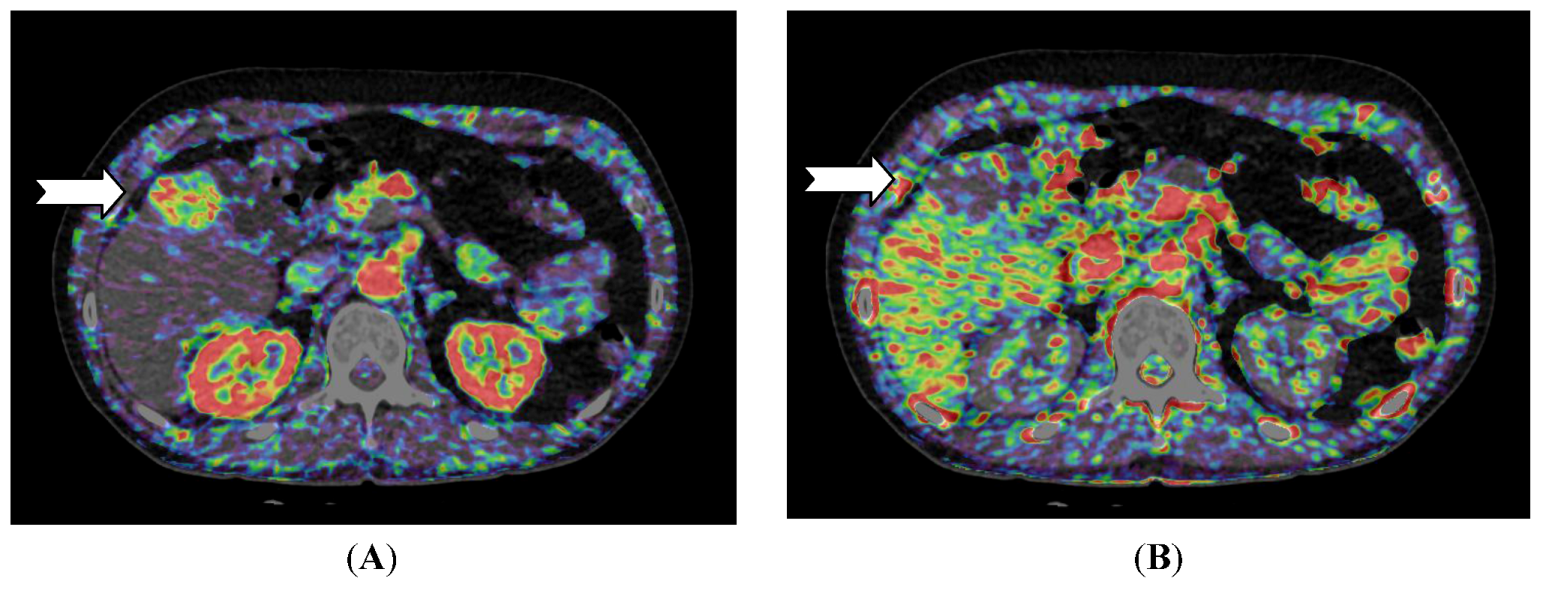

For pancreatic lesions, studies have shown that adenocarcinomas have a lower perfusion compared to normal pancreatic tissue [42,43]. For neuroendocrine tumors in the pancreas, D’ Assignies et al. [33] showed a higher perfusion and a positive correlation between blood flow and MVD (Figure 4).

Figure 4.

CT perfusion examination of a 63-year-old male with a pancreatic mass. The tumor has a neuroendocrine component and CT perfusion shows higher blood flow (110.2 mL/min/100 mL) (arrow) compared to the normal pancreatic tissue (83.7 mL/min/100 mL) (B). The patient has stents in the common bile duct (A) which causes image and perfusion artifacts in the pancreatic head. (Images reconstructed with Vitrea 6.2, Vital Images A Toshiba Medical Systems Group).